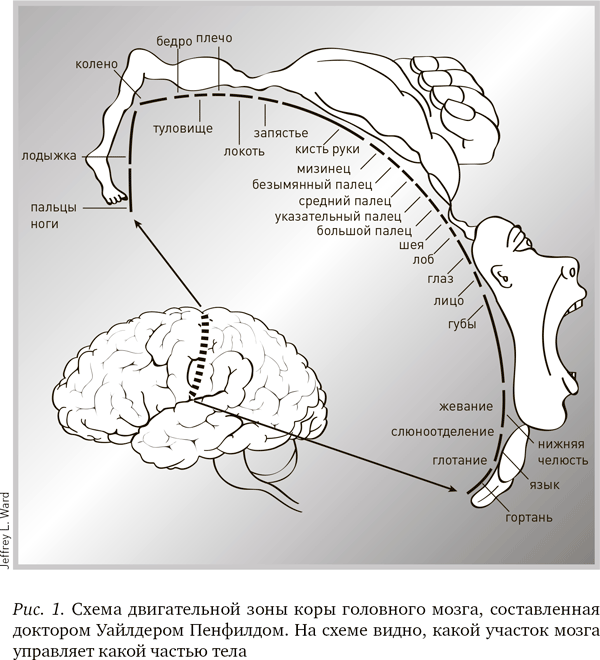

Доктор Пенфилд обратил внимание, что на стимуляцию определенных частей коры мозга при помощи электрода реагируют различные части тела. И внезапно понял, что может нарисовать приблизительный план соответствия участков коры мозга телу человека (рис. 1). Рисунки у него получились настолько точными, что их до сих пор используют почти в неизменном виде. И на ученое сообщество, и на публику они произвели очень сильное впечатление. На одной из схем можно видеть, какая приблизительно область мозга отвечает за какую функцию и насколько важна для организма эта функция. К примеру, кисти рук и рот для человека жизненно важны, на их управление отводится значительная доля мозга, тогда как нервные рецепторы спины на схеме почти незаметны.